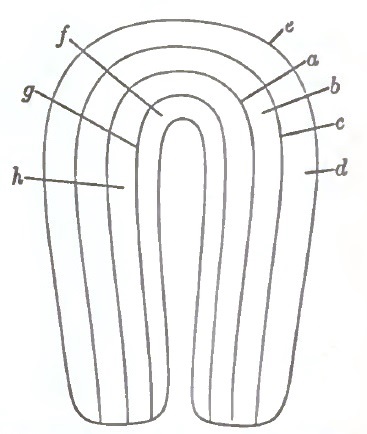

| 25. | DIAGRAM SHOWING MUSCULAR STRATA OF UTERUS, AS DIVIDED FOR CLINICAL PURPOSES |